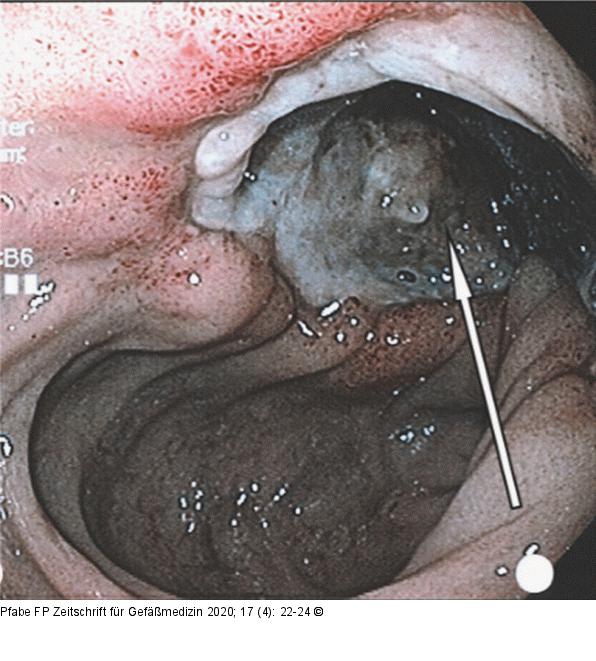

Abbildung 6: Duodenum Ösophagogastroduodenoskopie: Blick ins Duodenum, Nachweis einer spontanen Pseudozystoduodenostomie (weißer Pfeil) mit Entleerung des Pseudozysteninhalts. |

Ösophagogastroduodenoskopie: Blick ins Duodenum, Nachweis einer spontanen Pseudozystoduodenostomie (weißer Pfeil) mit Entleerung des Pseudozysteninhalts. |